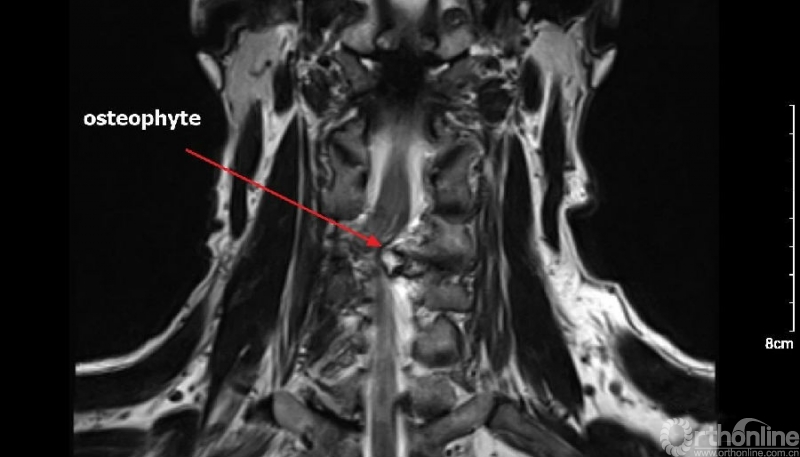

入院查体患者四肢肌张力高,双侧hoffman阳性。CT及MRI检查提示C4/5左侧关节突内缘有一巨大骨块(15mm*16mm),相应节段椎管严重狭窄。椎管内骨块的前端还有一游离骨块。

影像学资料

3.对侧先椎板切除减压给神经结构一缓冲空间更加安全,并且整个骨块的内侧及上缘、下缘清晰可见。